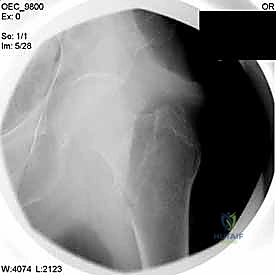

2. الرد المغلق تحت جهاز الأشعة (Closed Reduction)

قبل إجراء أي شق جراحي، يقوم الدكتور هطيف بسحب الساق وتدويرها بمهارة فائقة لإعادة العظام المكسورة إلى مكانها الطبيعي (المحاذاة التشريحية). يتم التأكد من ذلك باستخدام جهاز الأشعة السينية المتحرك داخل غرفة العمليات (C-Arm Fluoroscopy). هذه الخطوة حاسمة، فالرد الجيد يعني التئاماً ممتازاً.

مجموعة من الصور الإضافية التي توضح مراحل دقيقة من العمل الجراحي المعقد الذي يجريه الأستاذ الدكتور محمد هطيف لضمان أعلى درجات الدقة الميكانيكية الحيوية: